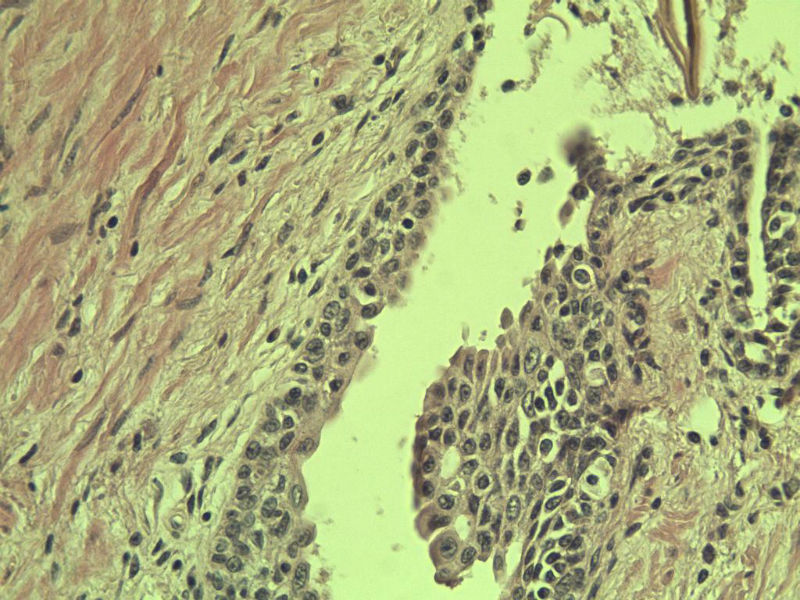

男 75岁 因排尿困难半年行前列腺切除术,体积 4 × 3 × 2.5 cm3,切面灰白,实性,质韧。请各位老师看看 有问题没? 谢谢了!

高级别上皮内瘤变,建议免疫组化:P63、34BE12、P504S

前列腺增生症伴鳞化

良性前列腺增生伴尿路上皮化生

呈巢上皮为尿道周围前列腺组织正常现象。尿路上皮-前列腺腺体过度。

良性。

前列腺增生伴尿路上皮鳞化及Brown巢形成,未见恶性。